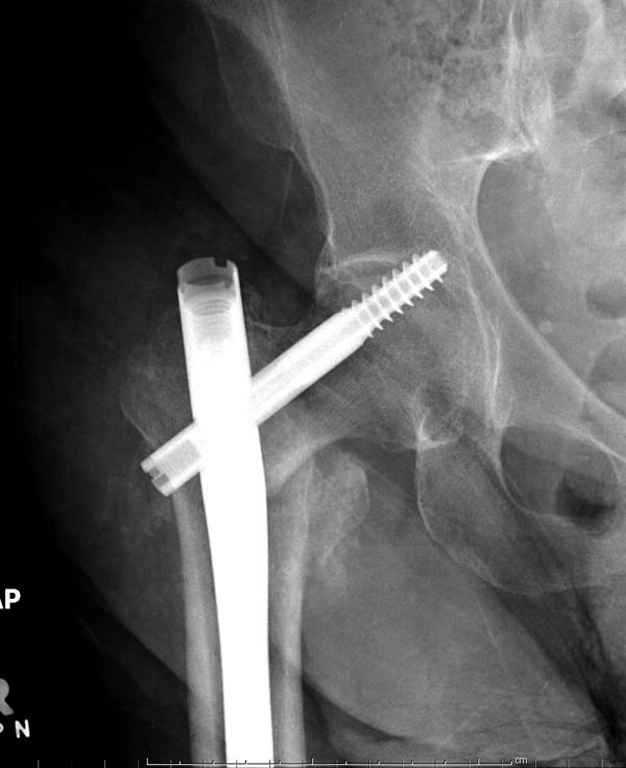

До выхода блокируемых гвоздей для фиксации косых подвертельных переломов в основном применяли Blade Plate. За счет уникальной конструкции создавался Fixed Angled Device, который соединял головку с диафизом, минуя зону перелома.

За счет особой конструкции клинка и подпорки (buttress) в диафиз создавалась стабильность, и предупреждалось скольжение по линии перелома. Перпендикулярная поверхность клинка предупреждала сгибательные и разгибательные смещения, и в сравнении с круглым винтом редко происходило прорезыванием.

Первые реконструкционные гвозди без блокировки винтов не смогли повторить преимущества, и из-за Z эффекта винтов происходило быстрое расшатывание.

С приходом менее агрессивных блокируемых цефаломедуллярных гвоздей (Gamma 3 и другие) изменилась тактика лечения. Несмотря на то, что вся стабильность держится вокруг одного блокирующего винта, в большинстве случаев гвозди приводили к успеху.

В данном случае в головке бедра и в вертлужной впадине огромный дефект, навряд ли удалением импланта или заменой на другой можно сохранить сустав.

Вашему вниманию представляется похожий случай, пациентке 70, осложнился в течение одного месяца после операции. Ревизия с заменой сустава, кабельная фиксация на трохантер. При установке в дистальном диафизе обнаружен тонкий кортикальный слой и сделана профилактика от возможного перелома аллографтом.